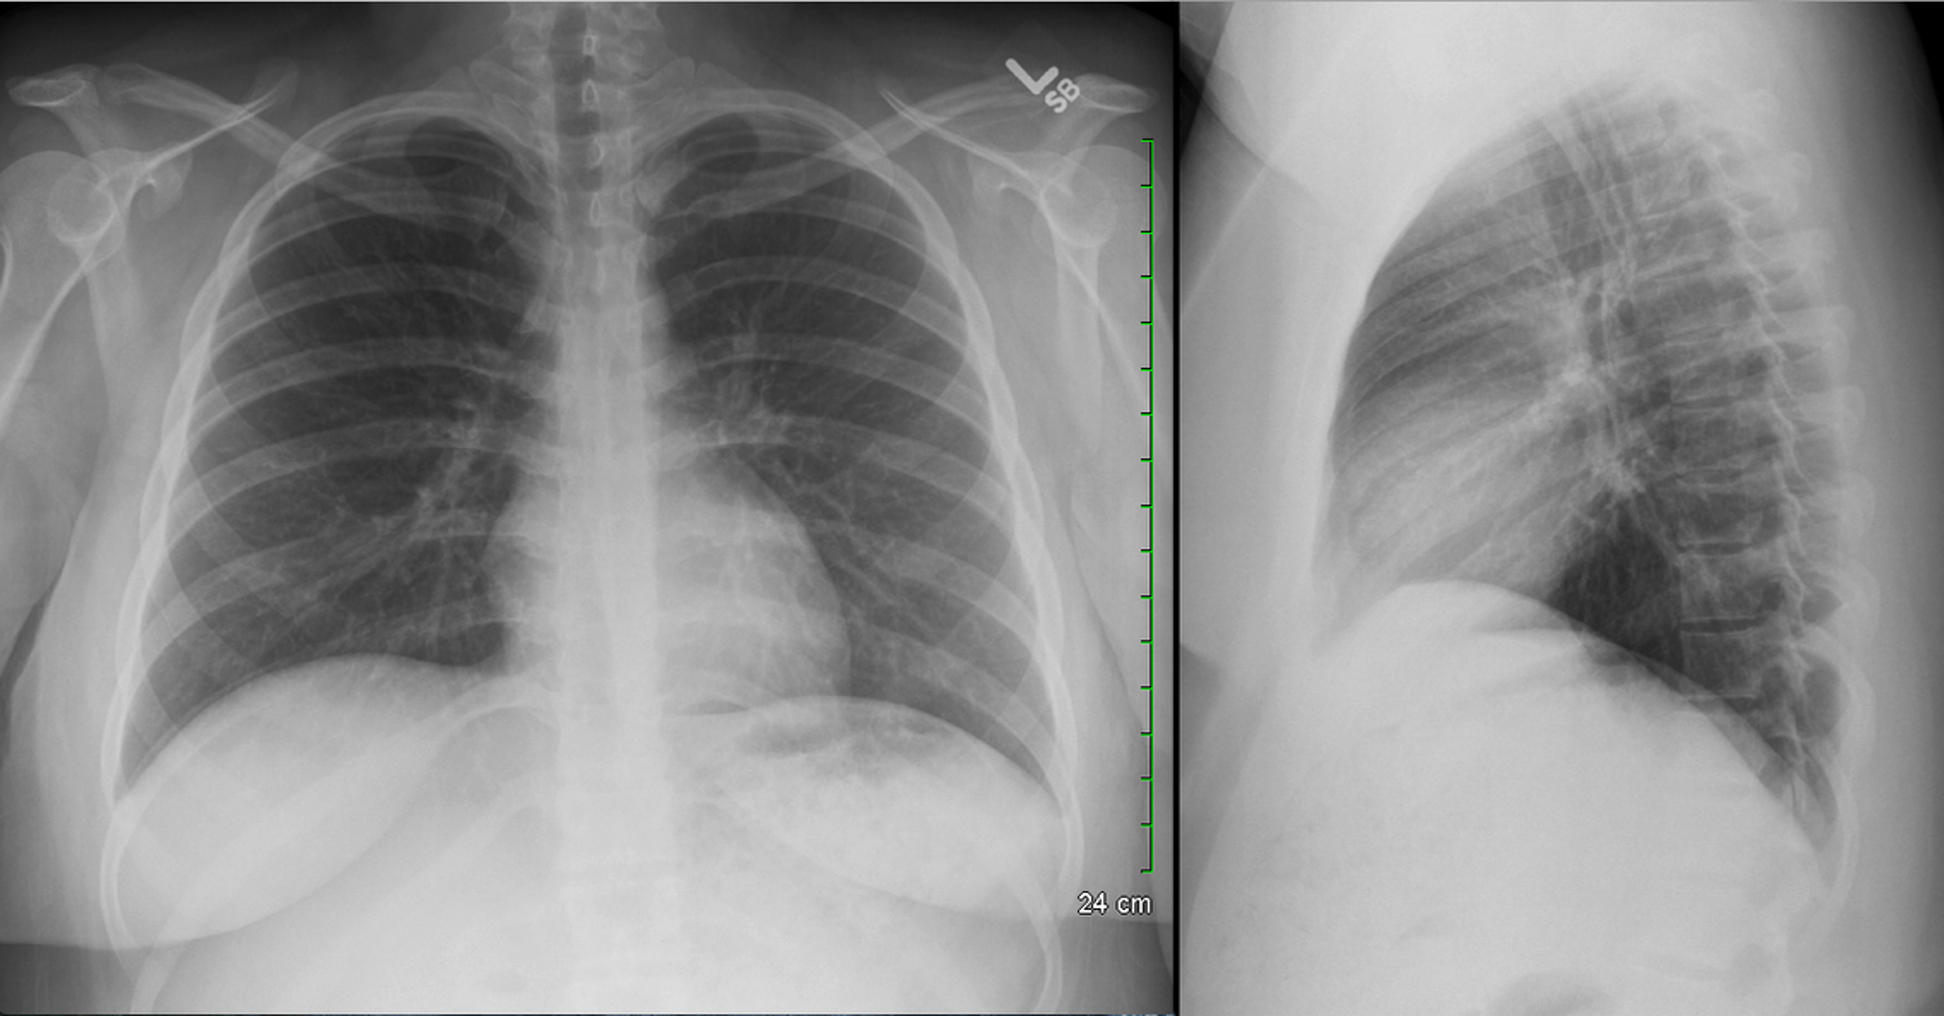

Normal CXR (PA & Lateral)

Flattened diaphragm on lateral CXR is a key sign of _________.

hyperinflation